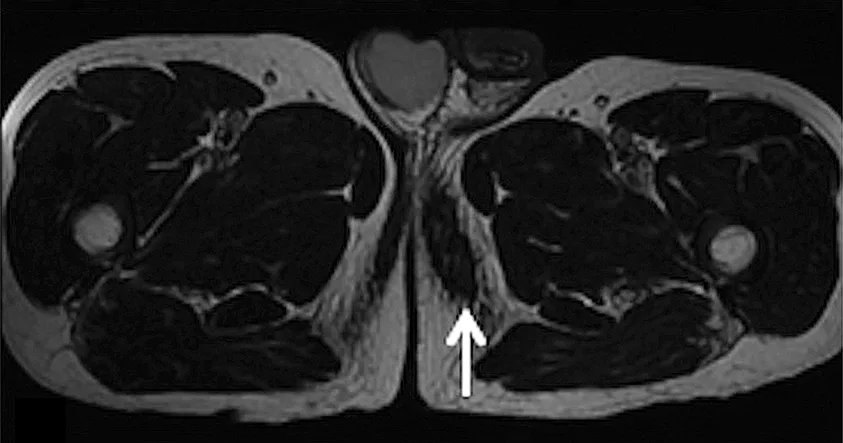

Une échographie ou une IRM peuvent aider à la confirmation du diagnostic en cas de doute [figure 10 (69)]. L‘échographie montre une masse hypoéchogène bien délimitée avec aspect hétérogène et un ombrage par réfraction (« edge shadow »), sans flux Doppler. En IRM, on observe le plus souvent un hyposignal T1 et un hypersignal T2 dans le périnée, juste sous la tubérosité ischiatique et un respect du tissu musculaire environnant (70). Les diagnostics différentiels cliniques varient en fonction de l’âge et du sexe du patient : kystes sébacés ou épidermiques, hydrocèles, varicocèles, adénopathies, hernies, anévrismes, lésions urétrales, syringocèles et diverses tumeurs (angiomyofibroblastomes, pseudosarcomes, tumeurs fibroblastiques…).

Figure 10 : aspect IRM axiale en T2 d’un « 3e testicule » chez un cycliste (69) (flèche)